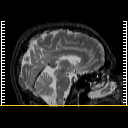

MR Study #5, March 10, 1991 -- Slice #1

[Home][Help][Clinical][Tour 1][Tour 2] Slice 1